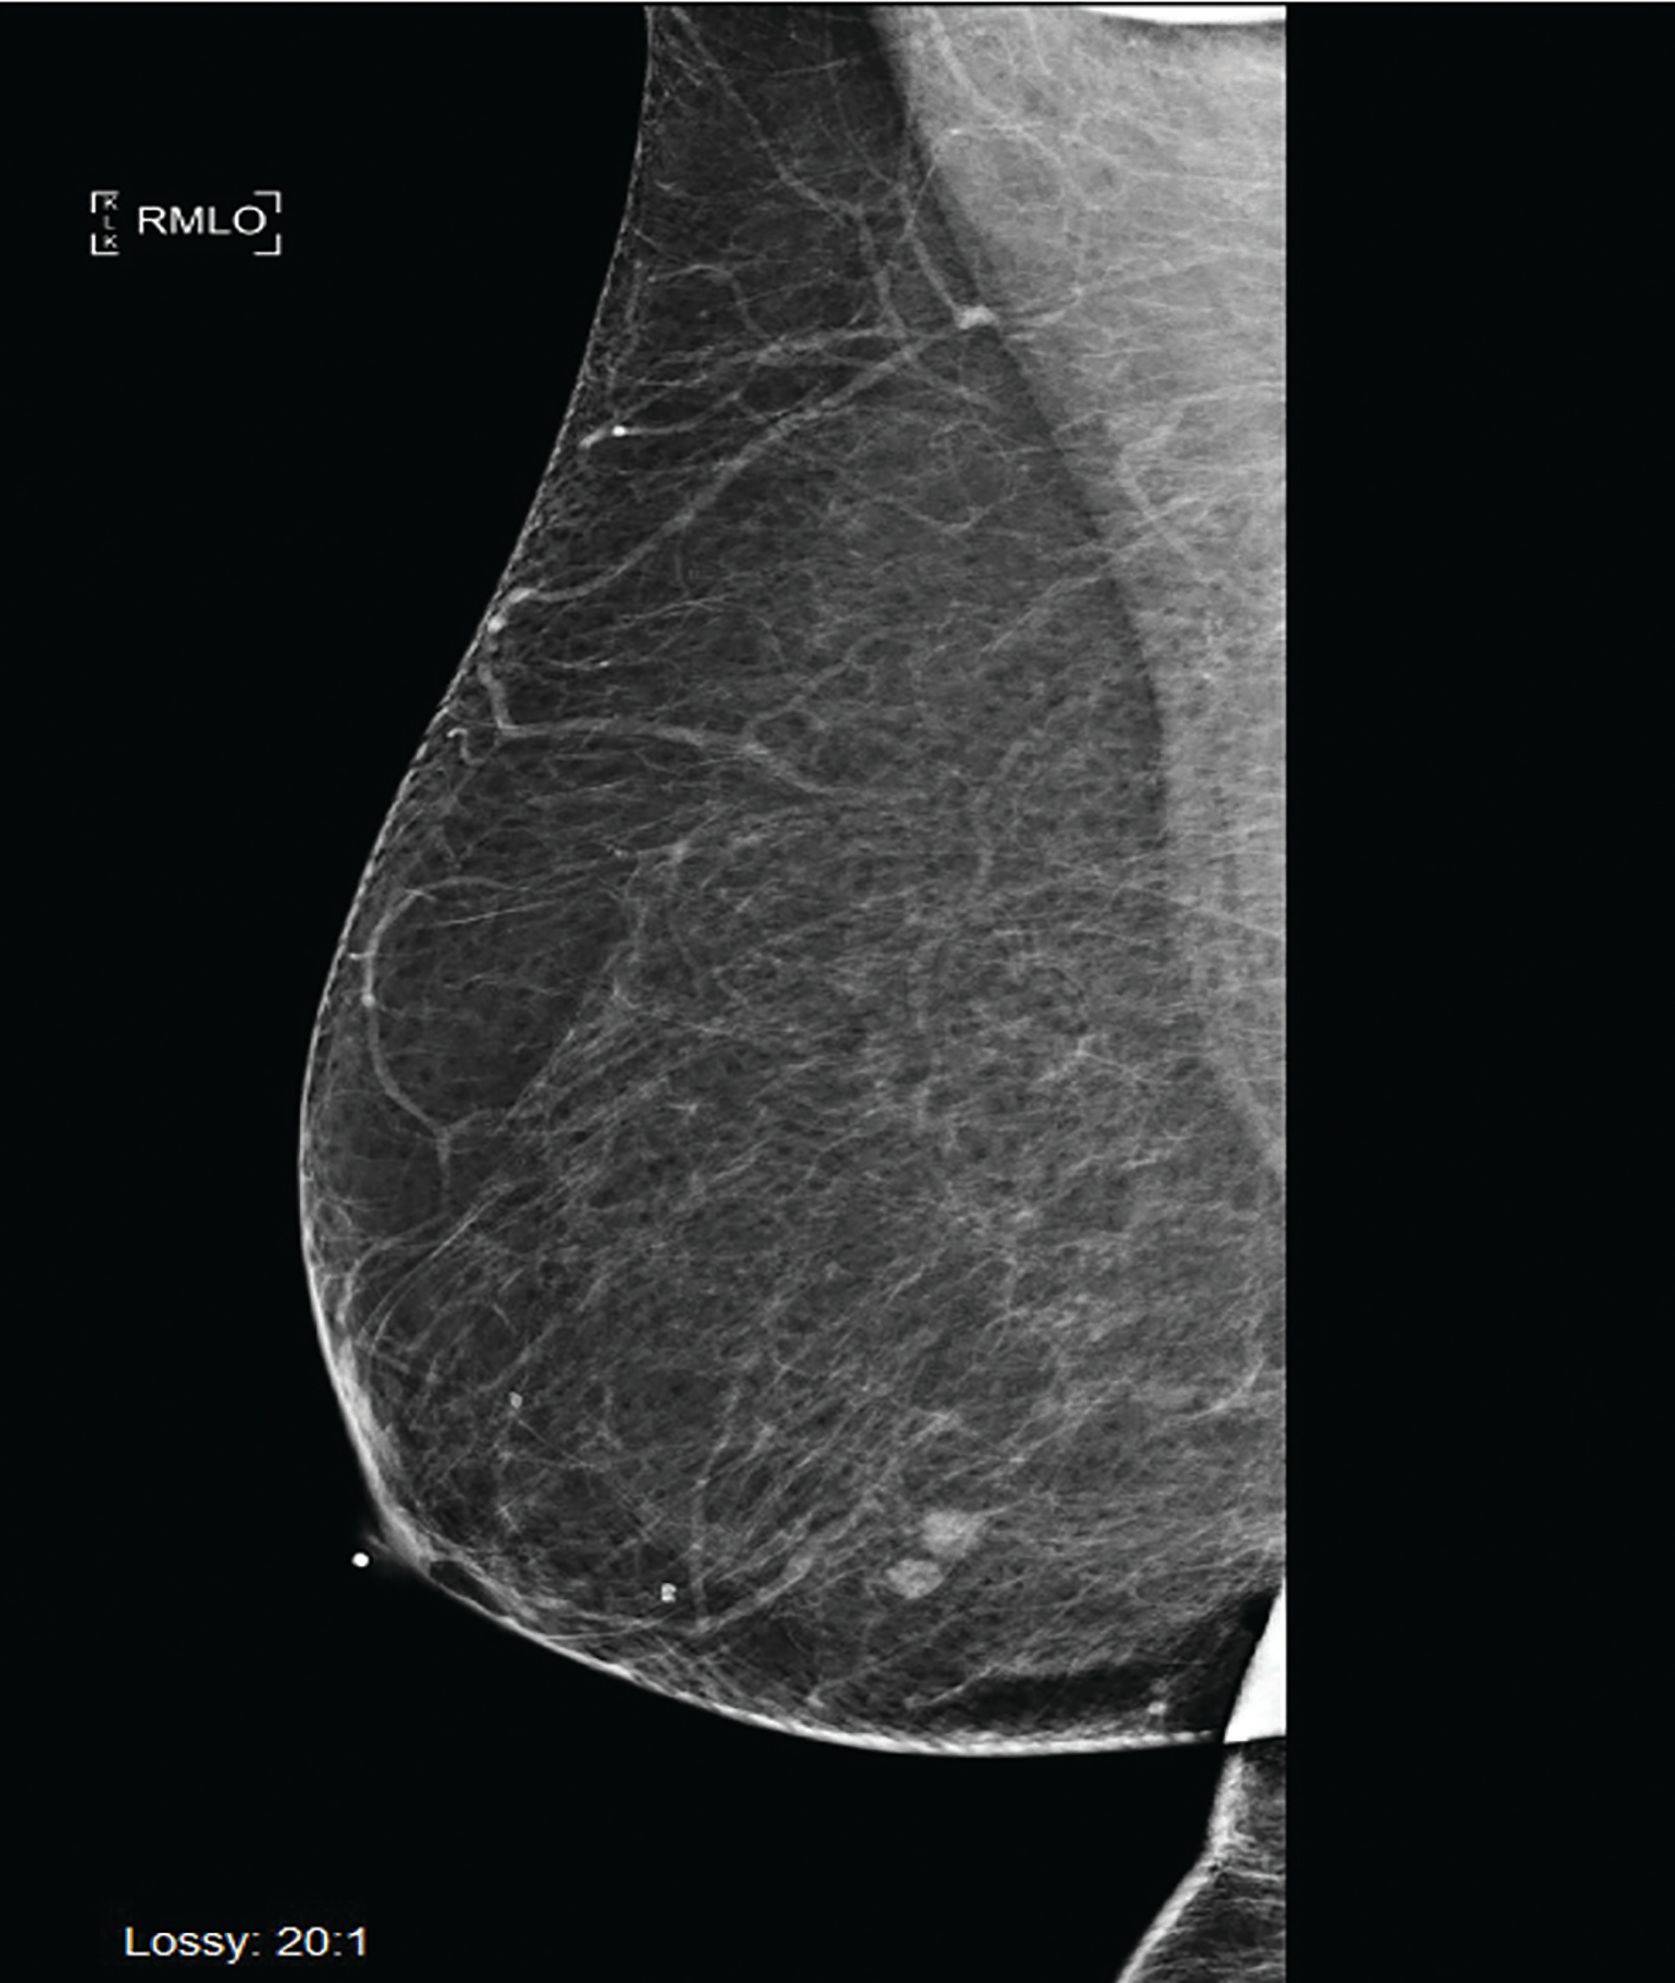

Six months following her surgery, a routine annual screening mammogram revealed 2 new adjacent nodules in the lower central right breast suspicious for breast cancer (Figure 3). Ultrasound guided biopsy of these lesions revealed adenocarcinoma consistent with metastasis from lung primary (Figure 4). A restaging PET-CT scan revealed new hypermetabolic lesions involving caudate lobe of liver, left adrenal gland, and bone lesions in left humerus, right scapula, and right ischium, which were totally asymptomatic (Figure 5).

Figure 4. Breast biopsy, invasive adenocarcinoma (hematoxylin and eosin stain). (A); Breast biopsy, invasive adenocarcinoma. Napsin A immunohistochemical stain (cytoplasmic positivity). (B); Breast biopsy, invasive adenocarcinoma. TTF-1 immunohistochemical stain (nuclear positivity). (C); Breast biopsy, Invasive adenocarcinoma. GATA3 immunohistochemical stain (negative). (D).